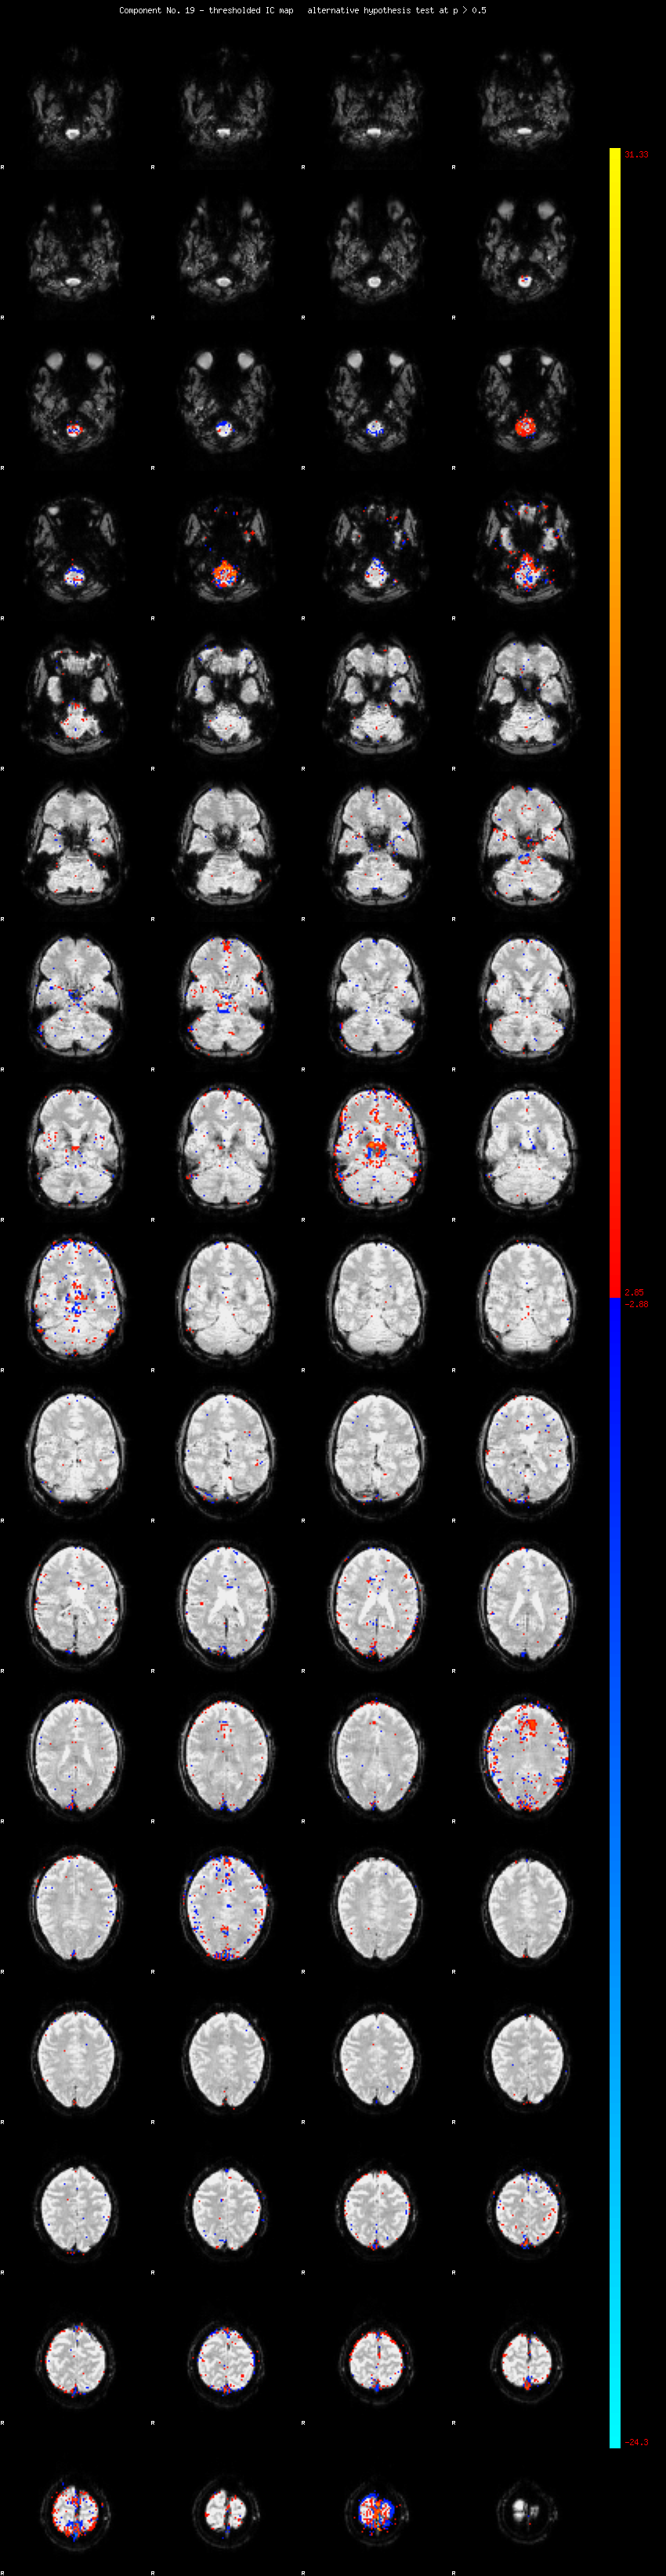

MELODIC Component 19

1.41 % of explained variance;     0.94 % of total variance

MMfit